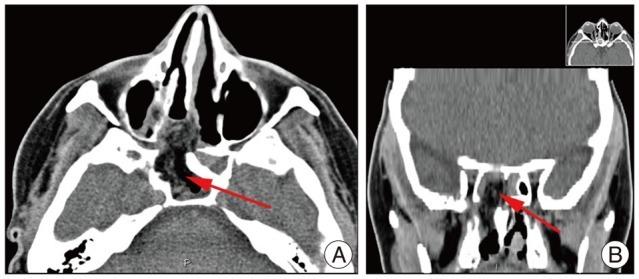

We report an uncommon case of a 45-year-old woman who presented with spontaneous rhinorrhea. A computed tomography (CT) scan of the head revealed an abnormally large sphenoid sinus associated with a parasellar bony defect (Sternberg's canal) through which magnetic resonance imaging could detect an encephalocele of the right temporal lobe. An endoscope-assisted trans-sphenoidal approach was performed and, with the aid of image guided surgery, reduction of the encephalocele was obtained and followed by surgical repair of the dural and bony defects. The postoperative course was uneventful and the cerebrospinal fluid fistula was closed as confirmed by the postoperative CT scan and by the absence of rhinorrhea. After three years of monitoring the patient remained asymptomatic.

我们报告了一例罕见病例,一名45岁女性出现自发性鼻漏。头部计算机断层扫描(CT)显示蝶窦异常增大,并伴有鞍旁骨质缺损(施特恩贝格管),通过该缺损磁共振成像可检测到右侧颞叶脑膨出。采用内镜辅助经蝶窦入路,并在图像引导手术的辅助下,成功将脑膨出复位,随后对硬脑膜和骨质缺损进行了手术修复。术后过程顺利,术后CT扫描及无鼻漏证实脑脊液瘘已闭合。经过三年的随访,患者仍无症状。